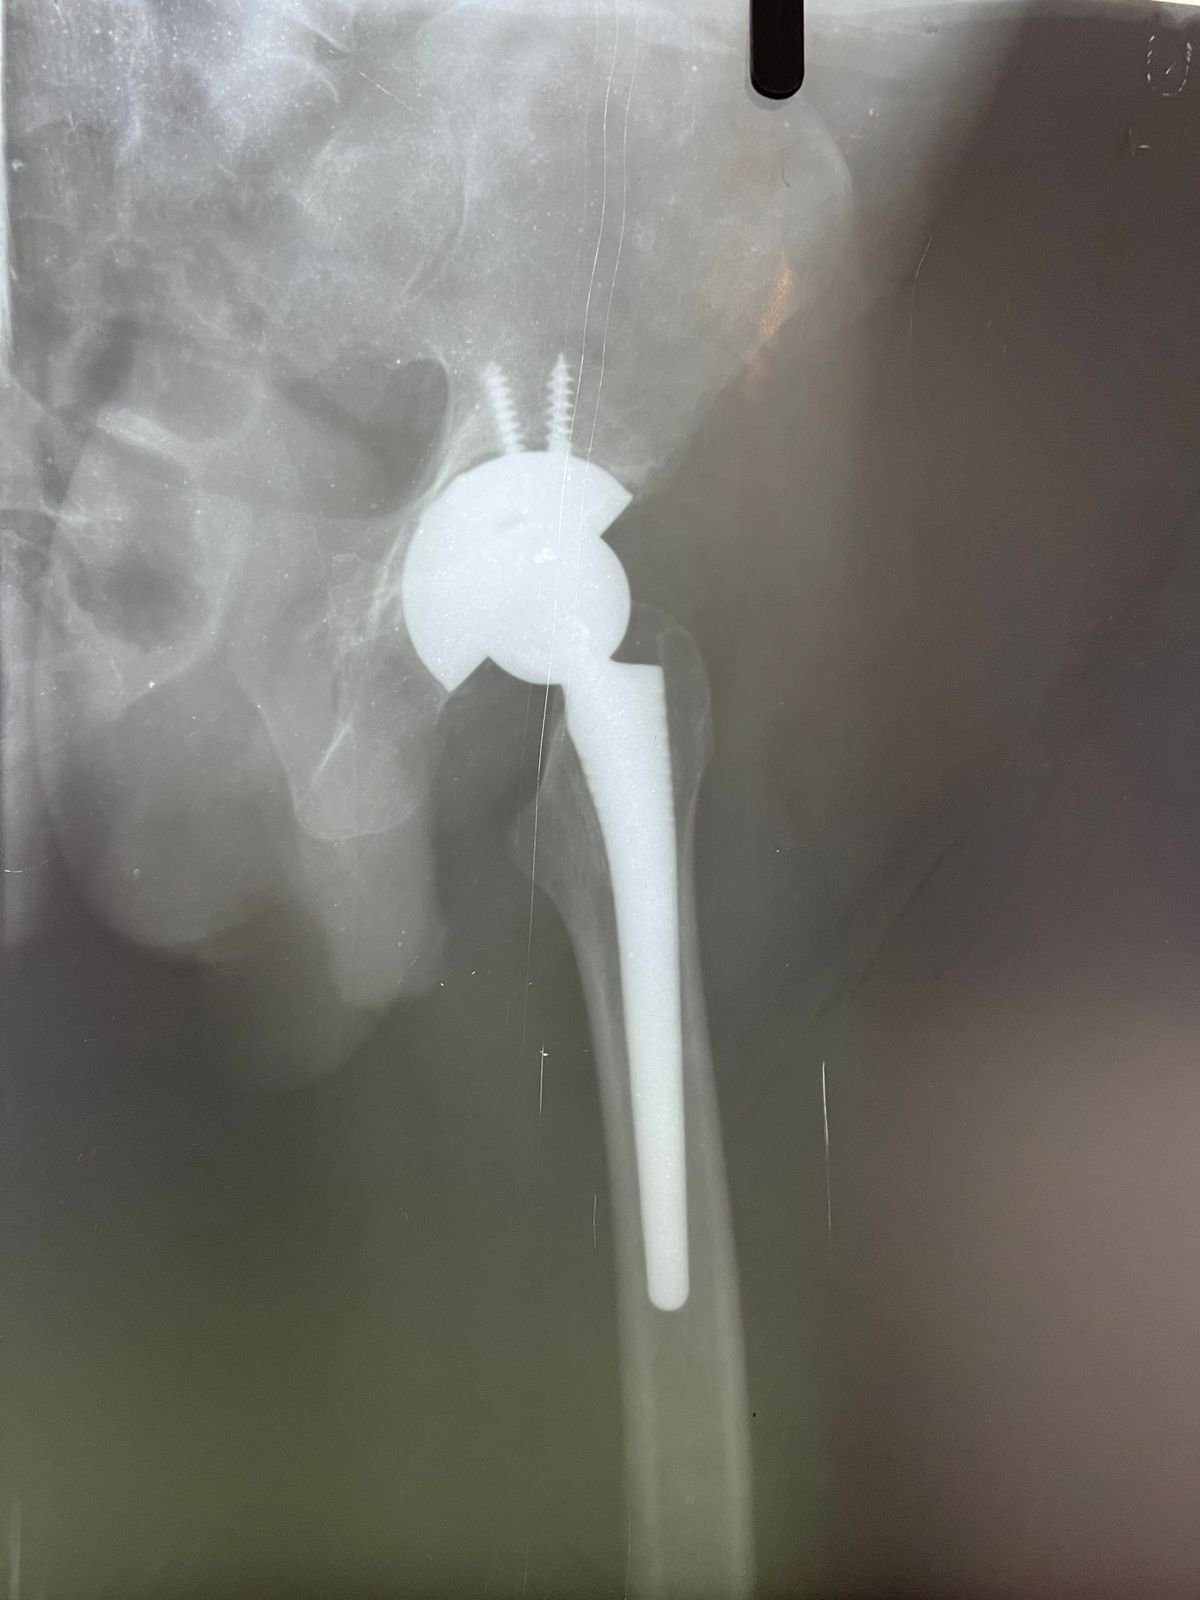

plaster & operation | Total Hip replacement case |

Non union with Broken DCS implant & revision